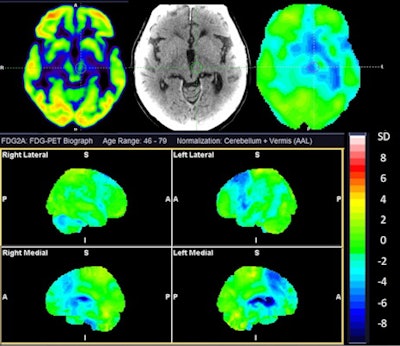

A team led by Naba Jawad Houssein demonstrated that cerebral F-18 FDG-PET scans helped differentiate between subtypes of atypical parkinsonism with significant sensitivity (> 80%) and specificity (> 90%). The results support the use of PET for the clinical diagnosis of atypical parkinsonism, the group noted.

While the diagnosis of atypical parkinsonism is based on clinical criteria, the researchers hypothesized that F-18 FDG-PET scans could provide more detailed data to separate the disorders based on uptake of FDG radiotracer in affected brain regions. Moreover, only a few studies have evaluated the sensitivity and specificity of the technique for this use, the researchers added.

The group identified 156 patients referred for a brain F-18 FDG PET scans between 2017 and 2019 for suspicion of atypical parkinsonism, with imaging analyzed by a nuclear medicine specialist with more than 10 years of experience in PET neuroimaging. The reference standard for comparison was each patient's follow-up clinical diagnosis.

The overall accuracy for correct classification was 74%, according to the results, with sensitivity and specificity for specific disorders as follows:

- Multiple system atrophy (n = 20): 100% and 91%

- Lewy body dementia (n = 26): 81% and 97%

- Progressive supranuclear palsy/corticobasal degeneration (n = 68): 62% and 97%